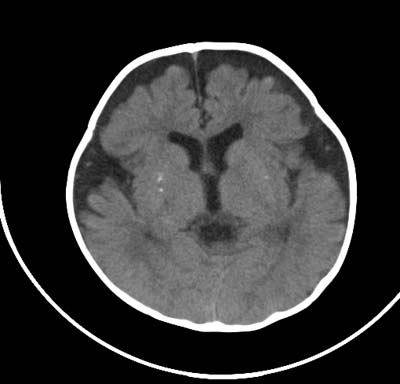

以下是引用影象小泰斗在2008-6-30 15:57:00的发言:[br]双侧额、颞部蛛网膜下腔增宽,纵裂加深, 支持外部性脑积水![br] 双侧基底节点状钙化!

以下是引用jiangjing在2008-6-30 17:19:00的发言:[br]双侧额、颞部蛛网膜下腔增宽,纵裂加深, 支持外部性脑积水![br] 双侧基底节点状钙化![宫内感染形成可能]